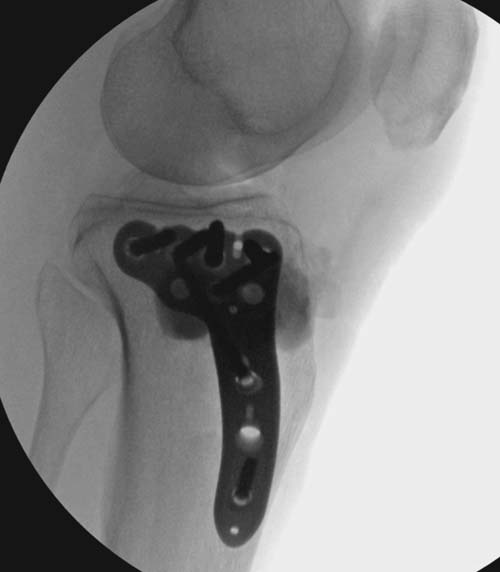

Устранение импрессии, костная аутопластика, остеосинтез опорной пластиной

задний кортекс не повреждён. Подойдёт рафтинговая пластина.

Учитывая, что у пациента молодой возраст(судя по рентгенограммам,абсолютно показано восстановление суставной линии: подменисковый доступ,подъём импренированной части мыщелка, костная аутопластика, остеосинтез, решение вопроса с мениском (шов либо парциальная резекция)).

Как подсказывают, можно с противоположной стороны приподнять сустав и заполнить костный дефект. Параллельные винты создадут достаточную опору, но иногда buttress plate за счет диафиза создает дополнительную стабильность. Структуральный материал для профилактики от раннего коллапса, и пластическим материалом служит более твердый синтетический материал (Osteoset DBM) или аутокость.